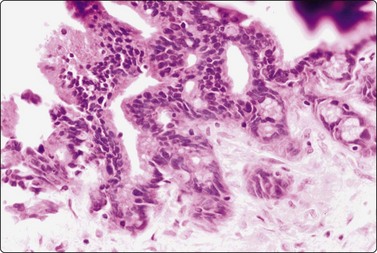

image image

Fig. 11.10 Adenocarcinoma (pancreas)

Well-differentiated adenocarcinoma; relatively mild nuclear atypia, but nuclear crowding and some dissociation, and in B a tendency to microacinar arrangement (A, MGG, HP; B, H&E, HP).

Fig. 11.11 Adenocarcinoma (pancreas) moderately differentiated

(A) Sheets showing disorganization and nuclear pleomorphism; background of necrotic debris (H&E, IP); (B) Disorganized clusters with some acinar arrangements (MGG, HP).

Criteria for diagnosis33,70-73

Disordered monolayer sheets, microglandular patterns, nuclear crowding; loss of cell cohesion,

Nuclear criteria of malignancy with contour irregularity and fairly distinctive margination of chromatin,

Moderate amount of cytoplasm, often mucin vacuoles, indistinct cell borders,

Evidence of necrosis, mitoses, macronucleoli and hyperchromasia in poorly differentiated forms.

Almost all adenocarcinomas arising in the pancreas are of ductal origin, without unique features permitting absolute distinction from carcinomas arising in the biliary tree. The characteristic FNB pattern is of crowded ‘drunken’ monolayered sheets, with moderately tall columnar palisading cells at luminal edges. Smaller aggregates commonly show rounded glandular structures with feathered edges, or three-dimensionality. Cytoplasmic borders may be very well demarcated in better-differentiated forms; in other cases, the monolayer sheets appear syncytial. The diagnosis of malignancy ultimately depends on nuclear features, which range from very subtle alterations to overly malignant criteria with decreasing differentiation (Figs 11.9-11.11). In an assessment of individual criteria by regression analysis, Cohen and colleagues extracted as most important: anisocytosis (4 : 1), nuclear enlargement and molding, with combined sensitivity of 98% using all three criteria to distinguish malignant from benign.70 In a similar study, Robins, Katz and Evans ascribed major status to nuclear crowding, contour and chromatin irregularity, minor status to single cells, mitoses and enlarged nuclei,33 requiring two major, or one major and two minor criteria for the definitive diagnosis of malignancy. Focusing specifically on the most challenging area, the recognition of well-differentiated carcinoma, Lin and Staerkel listed the following features: nuclear enlargement > 2 rbc (99%), anisonucleosis 4 : 1 (97%), nuclear membrane irregularity (97%), and crowding/overlapping/three-dimensionality (92%).73